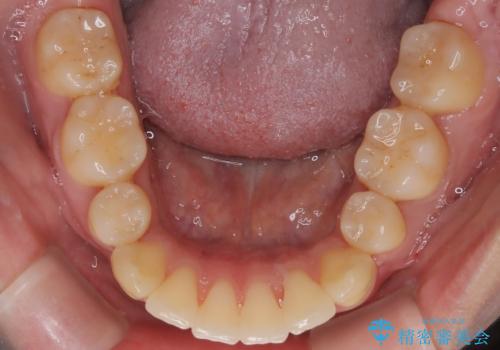

- 前歯の突出が強く、口元が前に出ている印象を改善するため、上下左右の第一小臼歯(4番)を抜歯する矯正治療を計画しました。抜歯により得られたスペースを利用して、前歯を後方へと移動させて整列します。治療には目立ちにくい透明な審美ブラケットとワイヤーを使用し、毎月1回の調整を行いながら徐々に歯を動かし、約2年で口元全体を整える計画としました。

前歯が前に出ているため口元が突出し、唇が閉じにくいなどの悩みを抱えておられました。治療にあたり上下左右の第一小臼歯を抜歯し、十分なスペースを作ることで前歯を効果的に後方へ移動させました。装置には透明で目立ちにくい審美ブラケットを採用し、治療中の審美的ストレスを軽減しました。定期的な調整を通じて無理なく確実に歯列を整え、前歯の突出感を解消。治療後は口元の印象が自然で美しく改善され、患者様には非常にご満足いただけました。